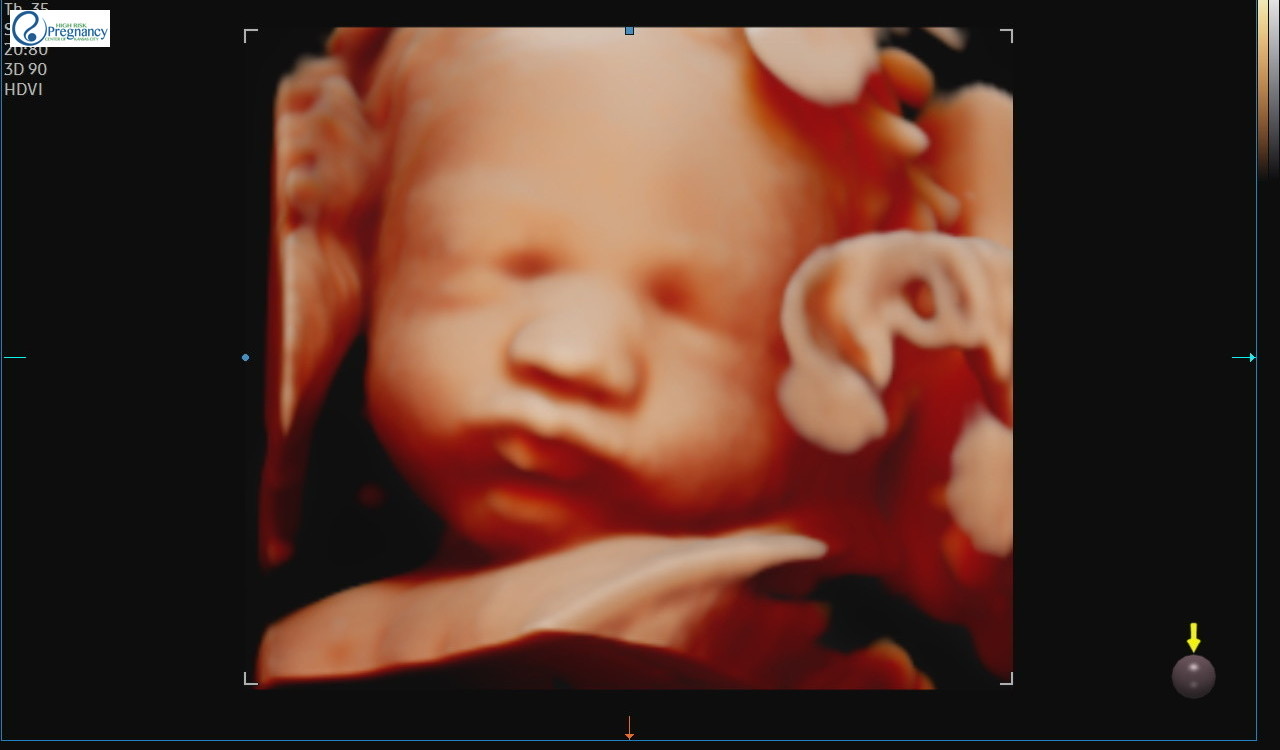

All three days I hoped and prayed that our little boy would keep on cooking. No surprises, no excitement. We obviously do not need to relive any deja-vu experiences. Thankfully on Monday afternoon I had one of my weekly ultrasounds. Getting to see your baby alive and well on an ultrasound definitely helps to curb the natural pessimistic feelings that accompany a stressful day. Baby boy looked great! One thing the doctor looks for at these ultrasounds is that your baby is practicing breathing for at least 30 seconds and that they perform a certain amount of movements. Baby boy passed both of these requirements right out of the gate! They also check for good blood flow through the umbilical cord, the heart rate (baby’s was 120 bpm), and other various things.

Look at those chubby cheeks! 😍